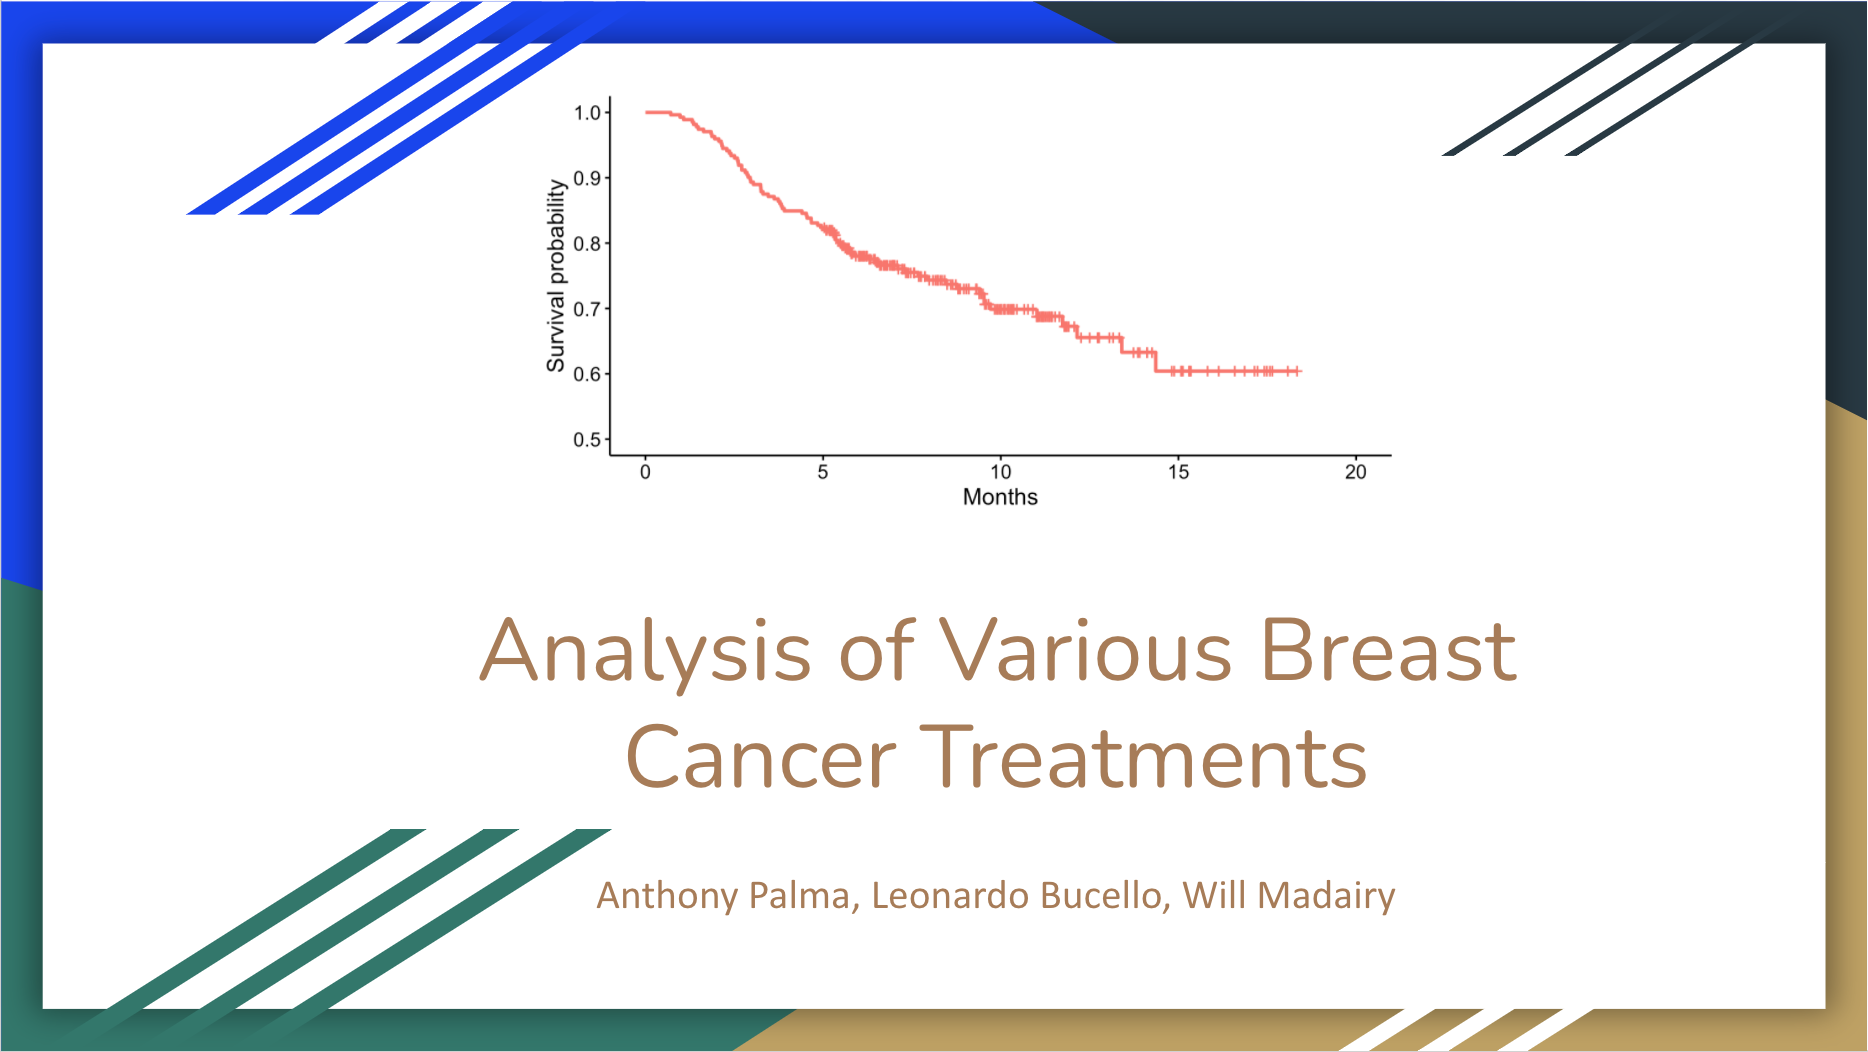

Analysis of Breast Cancer Treatments

Will Madairy ’21 (Charlotte, North Carolina),

Applied mathematics & statistics

-

How do differing breast cancer treatments compare in effectiveness? When considering which treatment is best, we would expect for more invasive procedures to lead to greater survival outcomes, but is this truly the case? Using data from the Netherland Cancer Institute, we were able to analyze survival outcomes across different treatments. In this analysis we compare outcomes for patients who underwent chemotherapy, hormonal, and amputation treatments and determine if any of the treatments leads to longer survival time compared to others.

What are the key factors affecting the survival of breast cancer patients?

Yiming Miao ’21 (China),

Applied mathematics & statistics, Computer science

-

Cancer has become a critical health problem. Among all sorts of cancer, breast cancer is the second common one in American women. Motivated by providing statistical insight into this disease, my teammate and I analyzed breast cancer data from Rotterdam Tumor Bank. This analysis aimed to investigate potential key factors affecting the survival time of breast cancer patients and also promote the awareness of breast cancer screening.

Factors that Affect Breast Cancer Survival — A Survival Analysis with Rotterdam Dataset

Zhenggang Tan ’21 (China),

Applied mathematics & statistics, Computer science

-

According to World Health Organization, Cancer is a leading cause of death worldwide, accounting for an estimated 9.6 million deaths in 2018. And amongst all cancer types, breast cancer(along with lung cancer) has the top cases of death: 2.09 million cases in 2018. According to the CDC, Breast cancer is also the second most common cancer among women in the United States, comprising 22.9% of invasive cancers in women and 16% of all female cancers. We think it would be interesting to take a look at survival and many related statistics of breast cancer.